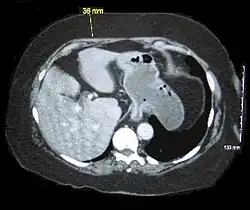

Abdominal computed tomography of an obese person showing excess abdominal adiposity | |